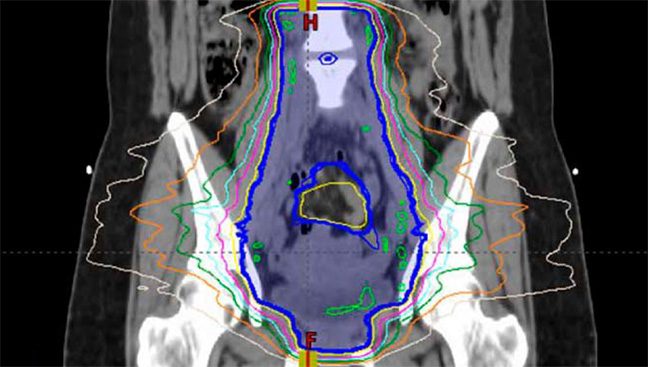

Planning is a multi-step process where clinicians analyze medical images to design a personalized radiation treatment plan that includes where the radiation is targeted, specific areas to avoid targeting and how much radiation will be delivered. The more complicated the case, the longer this process can take.

For many cases, however, the process is relatively routine. This makes radiation planning an ideal process for artificial intelligence (AI) to assist.

“This is something that AI is very good at,” Court says. “The algorithms we have developed can quickly take CT scans and develop very accurate treatment plans so that all the clinic has to do is review the plans and sometimes make minor changes instead of developing entirely new plans for each patient.”

To use the platform, clinicians upload a CT scan and complete a service request form, the deidentified data is then uploaded to the Radiation Planning Assistant servers. For complex cases, the system first does the contouring plan, which is then reviewed and finalized by the clinician before the system delivers the final treatment plan. For simpler cases, the plan is automatically created without this step. Once the plan is sent back to the clinician, they recalculate the dosages and make any necessary edits before the plan is utilized in the clinic.